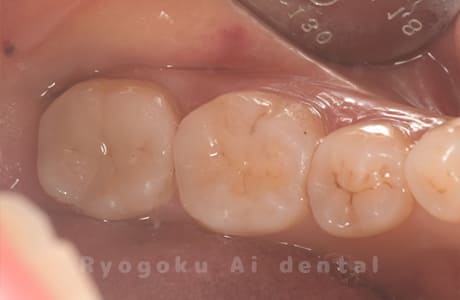

Case08

-

- 原因

- 虫歯

- 治療内容

- セラミックインレー

- 治療費用

- 77,000円

奥歯の黒い点が気になるということで来院された患者さんです。白い詰め物を外したところ、虫歯が中で大きく広がっていたため、患者さんと相談し、セラミックインレーで治療を行いました。

<リスク・副作用>

過度の咬合や衝撃で割れることがあります。